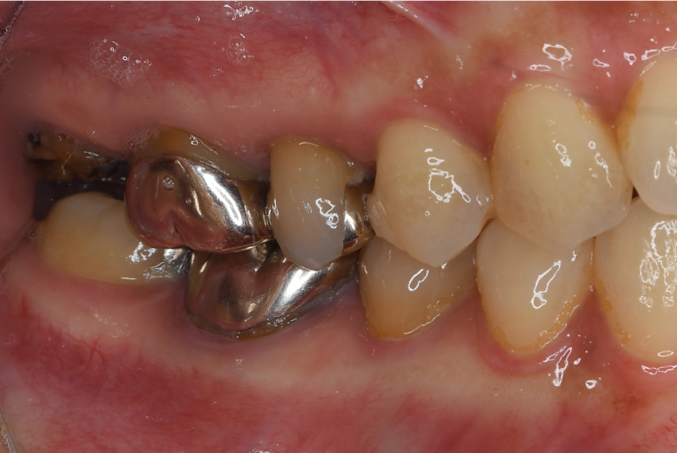

症例1

| 項目 | 詳細 |

|---|---|

| 患者様データ | 30代 女性 |

| 来院時の主訴 | 「右下の歯の治療後から違和感が続いている。」 |

| 医院の診断 | 虫歯の再発、慢性根尖性歯周炎、近心根パーフォレーション |

| 通院期間 | 6ヶ月 |

| 来院回数 | 8回(定期的なチェック含む) |

| 治療費 | 240,000円(税抜) 《内訳》 精密感染根管治療100,000円、ファイバーポストコア20,000円、セラミック治療120,000円 |

| リスクと副作用 | ①根管治療歯は長期的には破折するリスク ②メインテナンスが必要 |

| ココがこだわりのポイント☝ |

ラバーダム防湿とマイクロスコープを使用して丁寧に治療を行いました。 再根管治療のため、殺菌性があり歯を補強することのできる根管充填材料を使用しています。 |